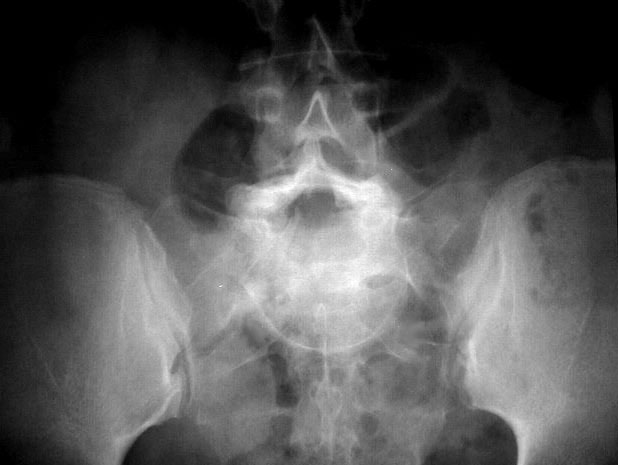

SIGNO DEL SOMBRERO DE NAPOLEÓN INVERTIDO

Signo de espondilolistesis L5-S1 en la radiografía anteroposterior de columna lumbar. El cuerpo vertebral de L5 desplazado y superpuesto al sacro da esta característica apariencia.

Este signo también lo hemos encontrado descrito como Signo de la línea de arco de Brailsford.

La misma imagen anterior con la imagen superpuesta del sombrero de Napoleón boca abajo.